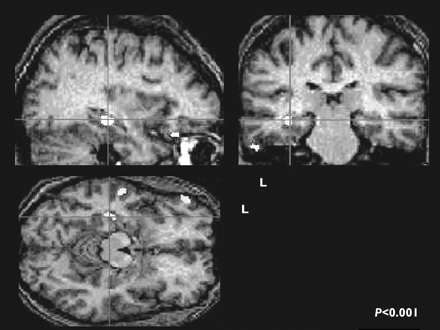

Green color reveals astroglial cell inflammation in the brain of an autistic child. The microglial cells (brown) are shown infiltrating the cerebellum of an autistic child. Blue cells are granular cells. Microglial cells "eat" (phagocytic) when there is neural damage or inflammation. The cerebellum is a major part of the brain that plays a significant role in motor function. Granular cells are a specific type of white blood cell which are part of the immune system.